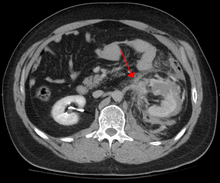

Blunt abdominal trauma (BAT) represents 75% of all blunt trauma and is the most common example of this injury.[4] 75% of BAT occur in motor vehicle accidents,[5] in which rapid deceleration may propel the driver into the steering wheel, dashboard, or seatbelt,[6] causing contusions in less serious cases, or rupture of internal organs from briefly increased intraluminal pressure in the more serious, depending on the force applied. Initially, there may be few indications that serious internal abdominal injury has occurred, making assessment more challenging and requiring a high degree of clinical suspicion.[7]

There are two basic physical mechanisms at play with the potential of injury to intra-abdominal organs: compression and deceleration.[8] The former occurs from a direct blow, such as a punch, or compression against a non-yielding object such as a seat belt or steering column. This force may deform a hollow organ, increasing its intraluminal or internal pressure and possibly lead to rupture.

Deceleration, on the other hand, causes stretching and shearing at the points where mobile contents in the abdomen, like bowel, are anchored. This can cause tearing of the mesentery of the bowel and injury to the blood vessels that travel within the mesentery. Classic examples of these mechanisms are a liver tear along the ligamentum teres and injuries to the renal arteries.

When blunt abdominal trauma is complicated by 'internal injury,' the liver and spleen (see blunt splenic trauma) are most frequently involved, followed by the small intestine.[9]